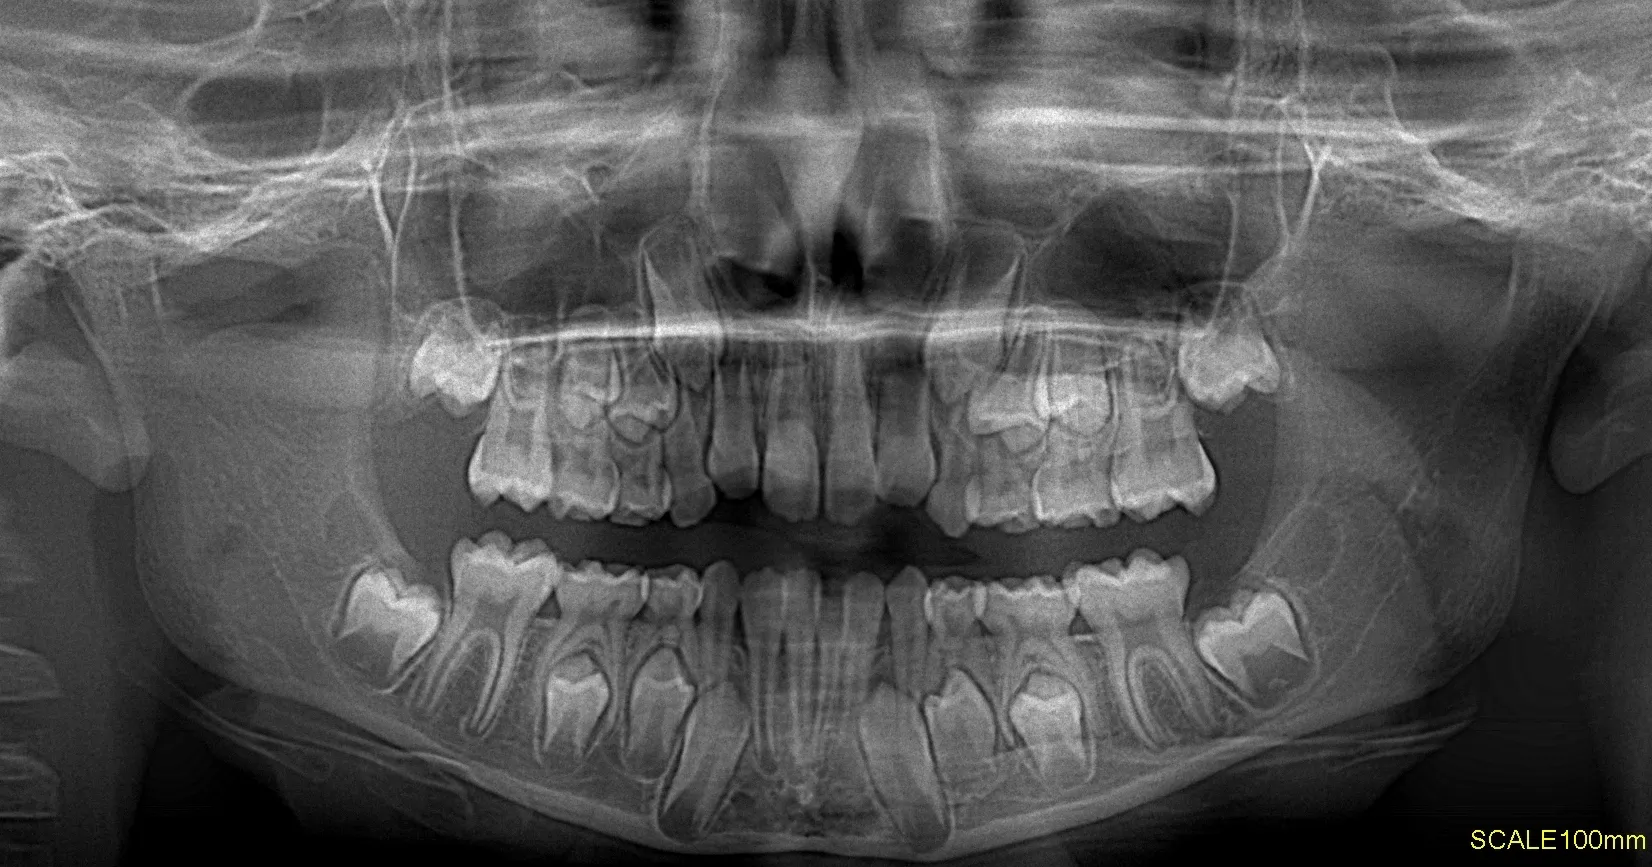

Radiografías Extraorales

Las radiografías extraorales permiten obtener imágenes completas de los maxilares, la articulación temporomandibular (ATM) y las estructuras faciales sin colocar el sensor dentro de la boca.

Realizamos estudios como radiografía panorámica, cefalométrica, de senos paranasales y de ATM, esenciales para tratamientos de ortodoncia, cirugía y diagnóstico integral.